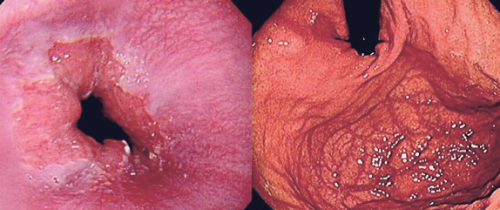

이번에는 많은 분들이 겪고 있는 역류성 식도염 증상, 치료방법, 역류성 식도염 예방법에 대해서 알아보도록 하겠습니다. 역류성 식도염은 소량의 위 내용물이 식도로 역류하는 질환으로, 역류 과정이 반복되면서 식도 내벽이 손상되고 염증이 생기는 증상입니다. 위산은 산성이 강해서 위에 있으면 괜찮은데 식도는 감당할 수 없는 조직이라 염증이 생깁니다. 위산 역류나 위염이 있을 때도 같은 통증이 나타날 수 있기 때문에 빈발하거나 만성적인 경우에는 병원을 찾아 전문의와 상담하는 것이 좋습니다.

역류성 식도염으로 속이 쓰릴 때 흉골 뒤쪽의 가슴에서 타는 듯한 느낌이 들며, 위의 구덩이에서 시작해 목 뒤 쪽으로 빠르게 상승합니다. 이 통증은 목과 팔 뼈의 중심부로 이어질 수 있는데, 식도염이 의심되면 상부 소화관 내시경 검사를 받아야 하는 이유입니다.

역류성 식도염을 치료하는 방법은 역류성 식도염 증상정도에 따라 달라질 수 있습니다. 우선 위에서 설명한 예방 수칙을 실천하는 등 생활 습관을 교정하는 것이 가장 도움이 됩니다. 다른 치료법으로는 내시경을 사용하여 하부 위식도 괄약근을 강화하여 역류를 줄이는 방법이 있으며, 이는 의사의 재량에 따라 시행됩니다. 위산 억제제, 위산 중화제, 위장 이완제와 같은 약물을 사용하여 증상을 완화할 수도 있으며, 의사가 처방할 수 있습니다.